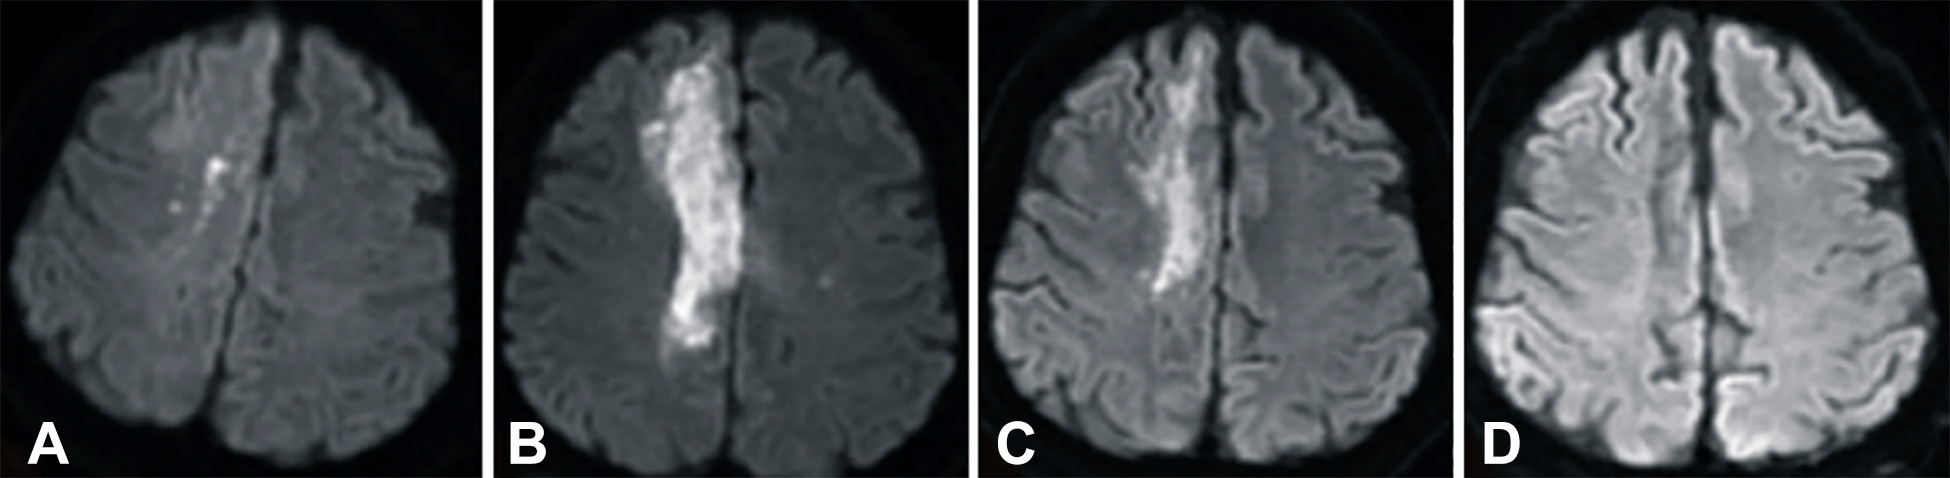

發病后2小時和8天行彌散加權成像(DWI)檢查,發現右側放射冠梗塞(白色信號增加),3個月后梗塞散在,6個月后消失(圖2A-D)。